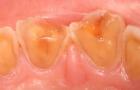

酸蝕症はこのように歯が溶け出して、悲惨なことになりますよ。

早めに来院しましょう。

みかんはかなり歯がしみますよね。

みかんをいつも1日に2個以上食べる人は胃液による酸蝕と同じくらいに歯が溶けますよ。みかんを毎日食べるのはやめましょう。

虫歯以外にも歯が酸によって実質欠損がおきることがあります。

それを酸蝕症といいます。つぎの場合です。

1、塩酸、硫酸などの強酸を取り扱う作業につく労働者

2、拒食、過食などによる嘔吐    胃液によって

3、胃の内容物の逆流によるもの   胃液によって

4、スポーツドリンク、みかん、酢、温泉水の強酸のよるもの

歯が虫歯で黒くなくても。歯が黄ばんでいたり、ゆがんだ形をしていたら早めに来院しましょう。